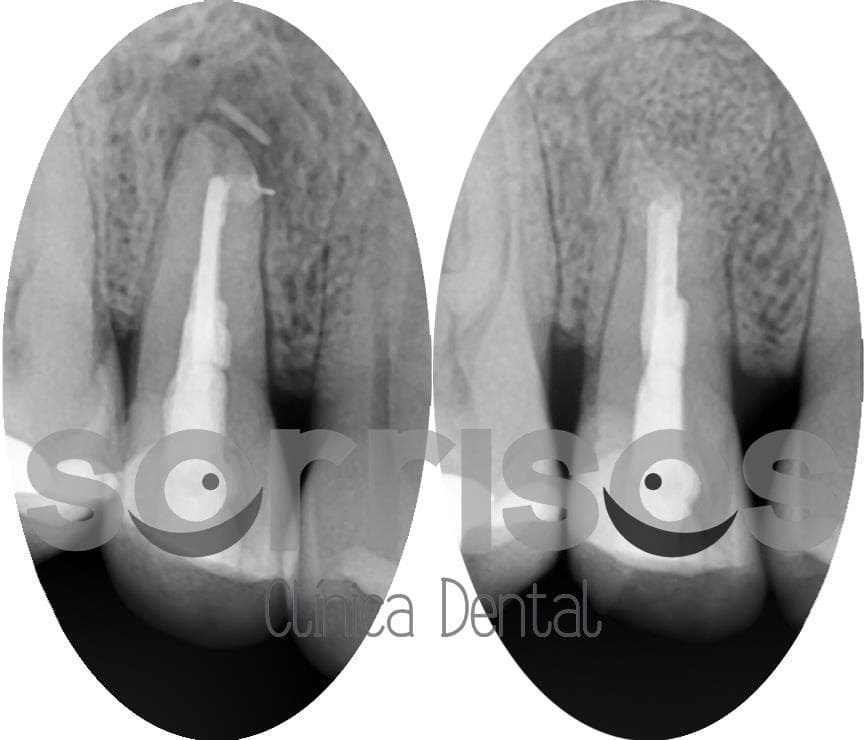

Se realiza la apicectomía, eliminando el tercio apical de la raíz, todo el tejido de granulación, se sella mediante MTA y se decide poner un biomaterial que ayude a mantener el espacio debido al tamaño de la lesión.